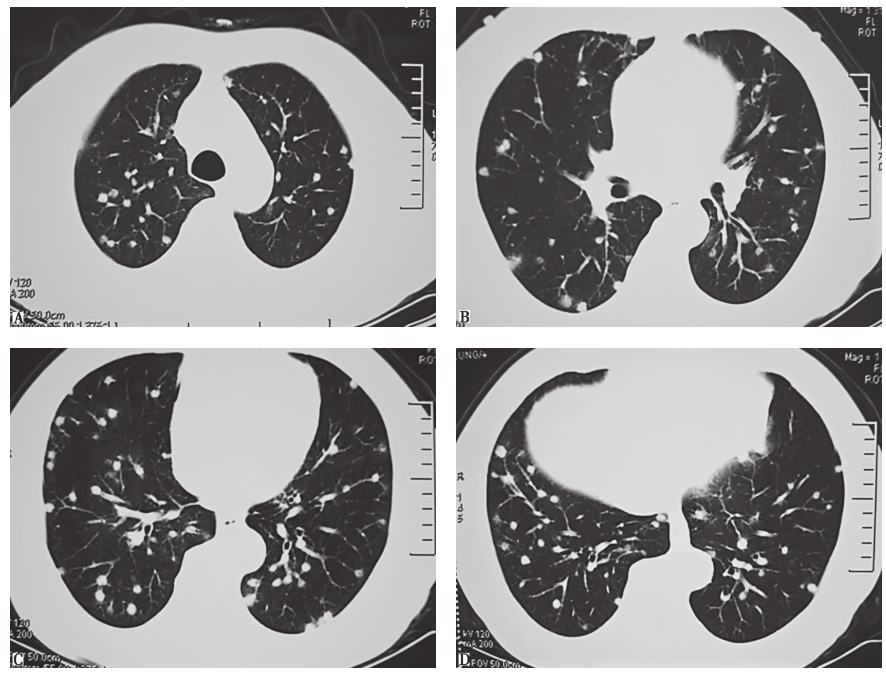

与患者(病例Ⅰ)同行的一名同事(以下称病例Ⅱ)也出现发热1天,回国后体检发现肺内多发结节影。病例Ⅱ临床信息如下:男,63岁,于2013年1月8日自觉发热伴乏力,对症治疗后症状很快好转;1月28日外院胸部CT发现双肺多发结节(图1),怀疑转移瘤;2月25日行胸腔镜肺活检,病理检查提示肉芽肿性炎症伴坏死;后转来我院进一步诊治。

图1病例Ⅱ外院胸部CT表现(2013-01-28)